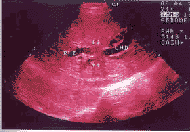

肝门部胆管癌超声的典型表现为:①肝内胆管扩张,可见扩张的左右肝管在肝门处截断,并见低、高或中等团状回声(图1);②胆囊空虚;③胆总管不扩张,胰头不肿大。

图1 肝门部胆管癌声像图